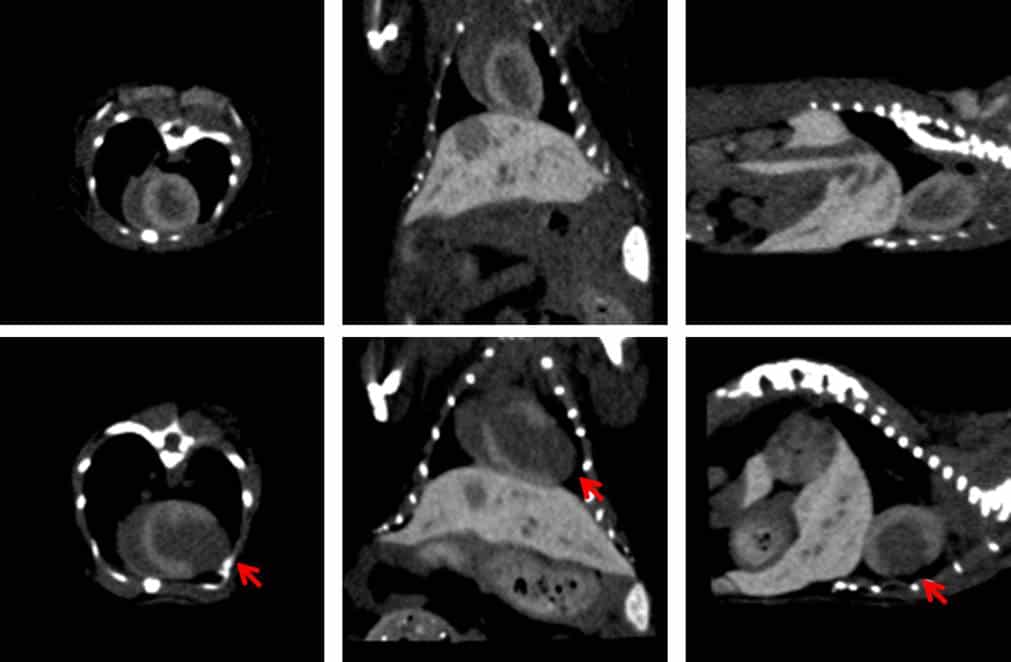

Left: Axial, coronal and sagittal CT images (from left to right) of a healthy mouse (upper row) and a mouse model of myocardial infarction (lower row) using ExiTron MyoC 8000. The red arrows indicate the non-enhanced infarct region.

Conventional CT contrast agents often provide limited contrast between myocardial tissue and blood, particularly in pathological conditions. ExiTron™ MyoC 8000 addresses this challenge by preferentially enhancing healthy myocardium while remaining sufficiently present in circulation to support cardiac imaging workflows. This behavior enables visualization of pathological regions such as infarcted tissue, which appear as non enhanced areas relative to surrounding myocardium.

After administration, ExiTron™ MyoC 8000 produces strong and stable myocardial contrast that supports detection and quantification of myocardial injury. The agent enables clear delineation of infarct regions and supports measurement of infarct size in murine models. Its pharmacokinetic profile allows investigation of functional cardiac parameters while maintaining image quality suitable for quantitative micro CT analysis. Complete biological clearance within approximately one day enables repeated administration in longitudinal study protocols.

Micro CT imaging studies using ExiTron™ MyoC 8000 demonstrate clear differentiation between healthy myocardium and infarcted regions. Time course analyses show distinct enhancement profiles in blood and myocardial tissue, enabling temporal assessment of contrast distribution and washout. These characteristics support reproducible imaging outcomes across cardiovascular disease models.